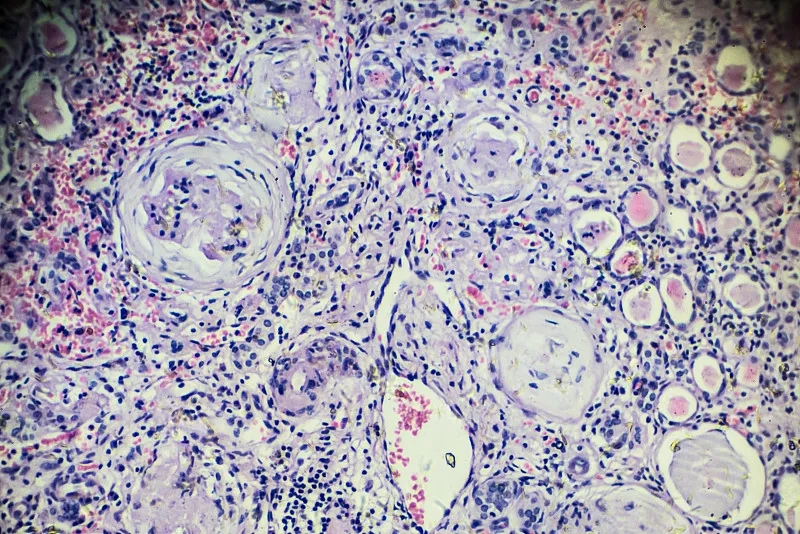

大約10%的MM患者在診斷時還患有CKD或急性腎損傷 (AKI),幾乎50%的MM患者在某個時候經歷過CKD或 AKI。大約10%的MM患者會出現需要長期透析的晚期 CKD,而腎功能損害 (RI) 與MM患者的死亡率和發病率較差有關。